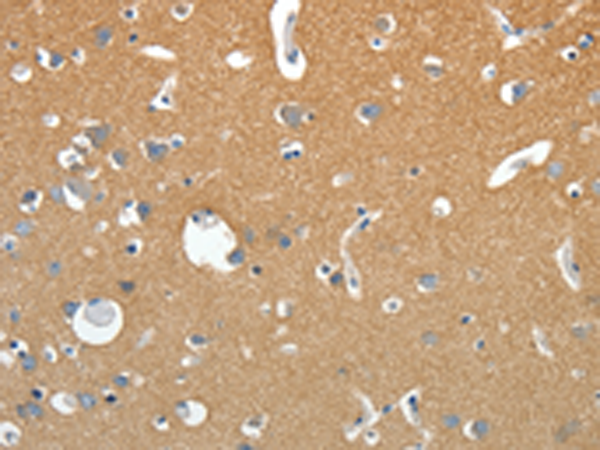

| IHC | 咨询技术 | Human,Mouse,Rat |

| Species Reactivity | Human, Mouse, Rat |

| Immunogen | Synthetic peptide of human SSTR4 |